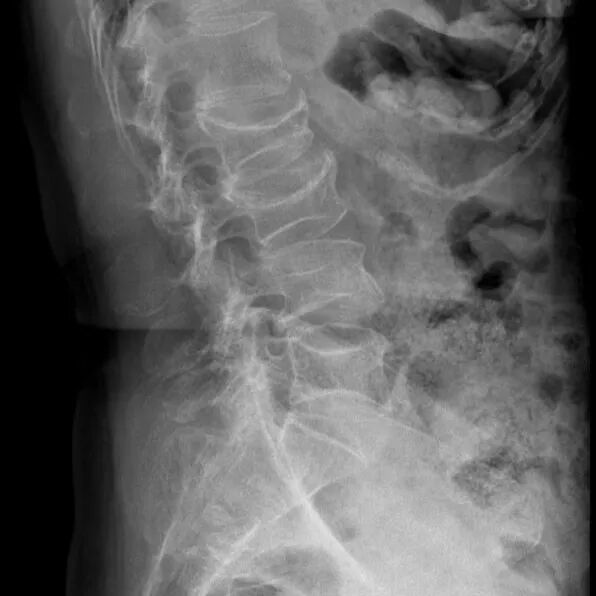

DR显示:腰椎压缩性骨折

身高变矮:比年轻时矮了3厘米以上,可能是脊柱压缩性骨折导致的。

慢慢驼背:脊柱无法支撑身体重量,逐渐变弯,形成“驼背”。